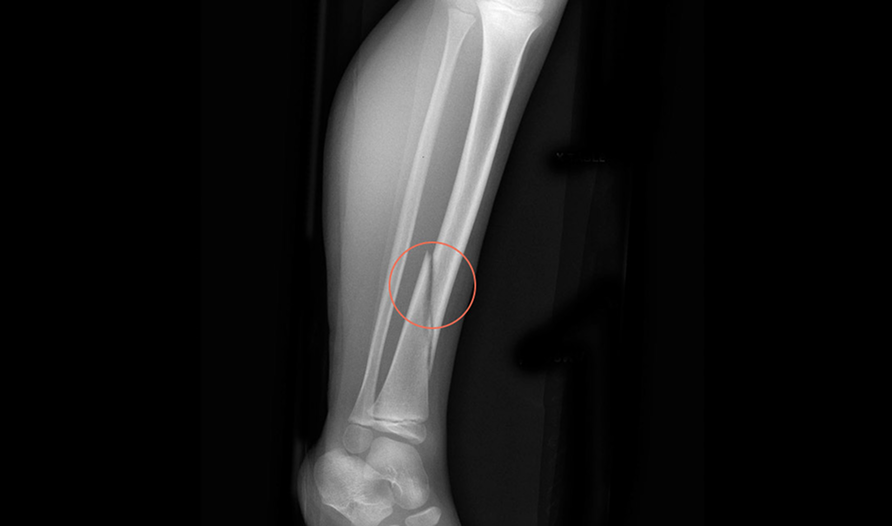

Rbfracture™

AI-powered, automatic detection of trauma-related findings